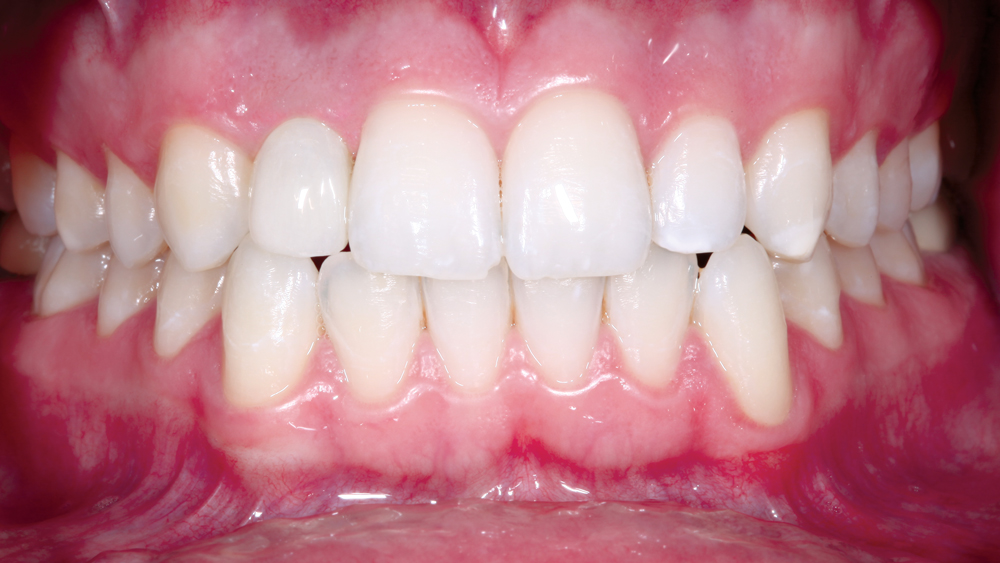

The following case illustrates the efficient, straightforward clinical workflow for placing Hahn Tapered Implants via guided surgery. A digital treatment plan is developed in which a 3.5 mm implant is positioned to support the ideal prosthetic outcome. An immediate provisional crown is designed in concert with the surgical guide and delivered at the time of surgery, helping to produce a predictable, highly esthetic restoration for a demanding case in the smile zone.

With the release of the Hahn Guided Surgery System, clinicians now have an efficient option for the digitally guided surgical placement of Hahn Tapered Implants. With simplified instrumentation, a streamlined surgical protocol, and support from a dental lab that ensures a restorative-driven approach is maintained throughout the course of treatment, the Hahn Guided Surgery System is a valuable tool for novice and experienced implant practitioners alike.